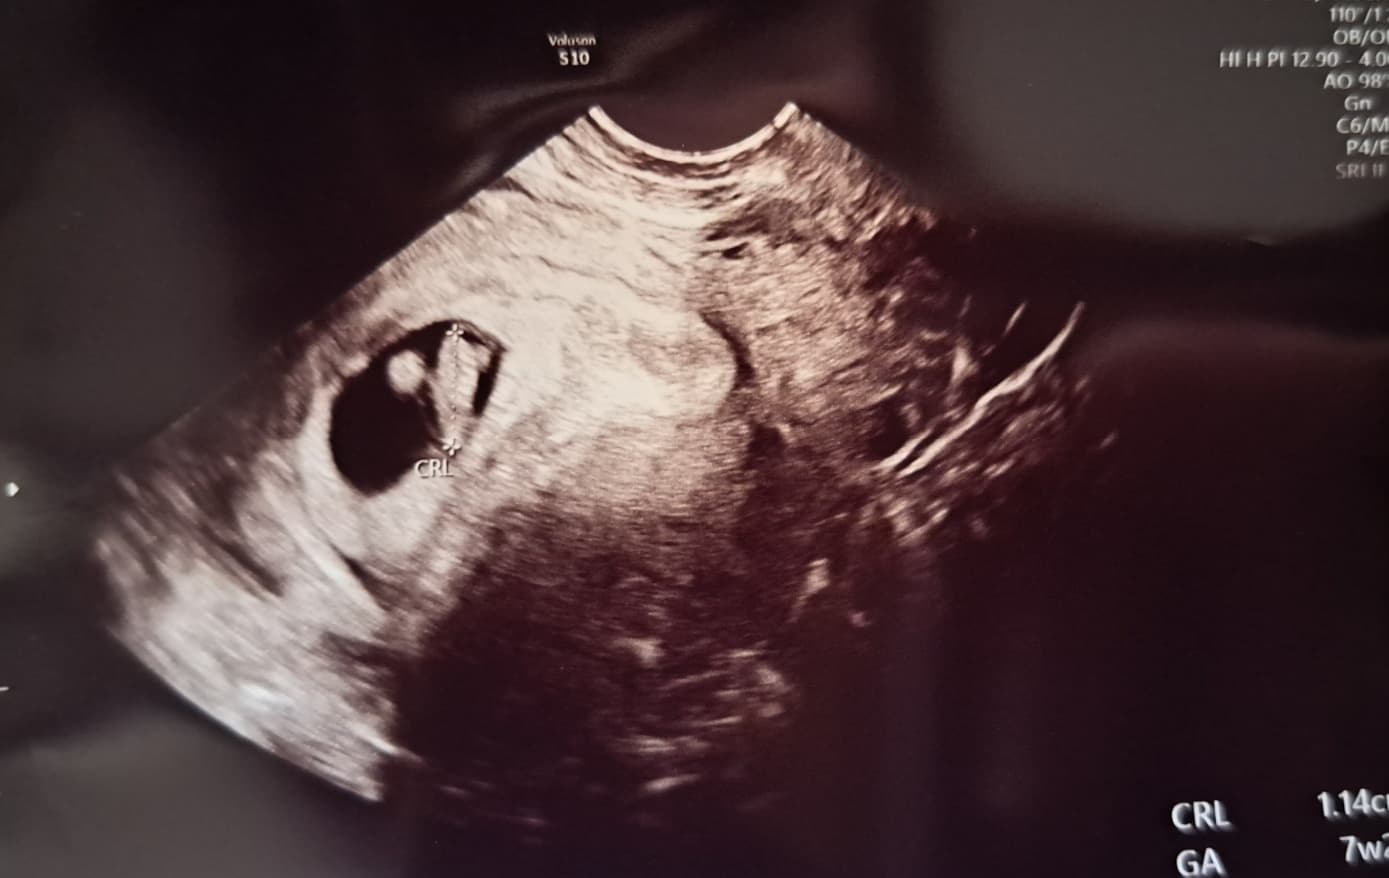

그런데 산부인과에 가서 상황들을 이야기하니 선생님께서 '임신같은데~' 라면서 초음파를 보니 진짜 임신이었던 거죠😲

임신 계획이 정말 1도 없던 시기라서 초음파 상으로 아기집도 보이고 심장소리도 들리는데 정말 기쁨보다 당황스러움이 더 컸던 기억이 나네요ㅋ

저는 임신인 걸 알고나서도 물혹이 계속 신경쓰여서 검진 갈 때마다 물혹 초음파도 같이 봤어요.

임신 10주 전까지는 물혹이 조금씩 커지다가 10주쯤부터 크기가 작아지기 시작했고,

니프티 검사를 할 즈음(14주?)에는 아기집 크기가 커져서 물혹은 초음파로도 안 보이는 정도가 되었어요.